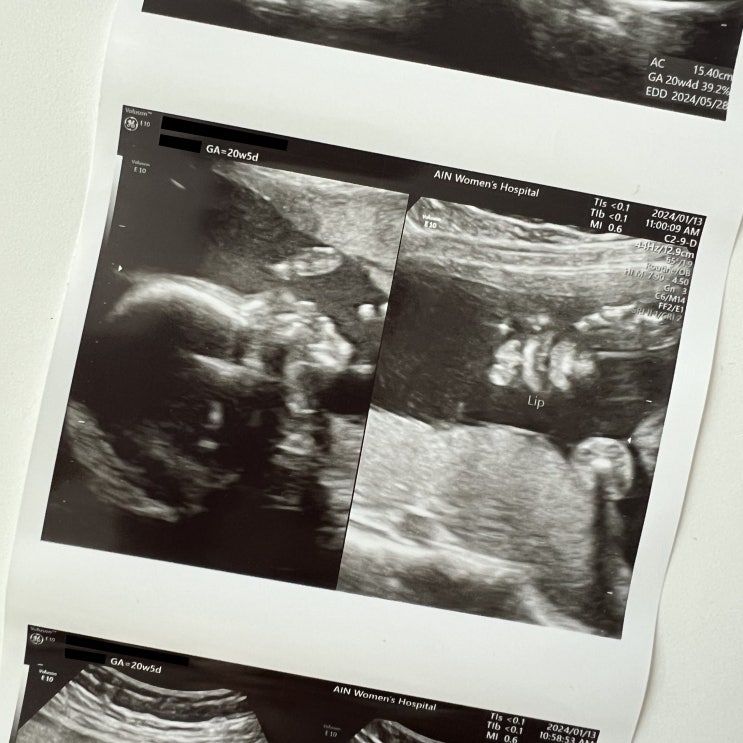

안녕, 안뇽! 20주 / 중기정밀초음파

2024. 01. 13 _ 20주 5일 16주 1일에 마지막 진료를 보고 거의 5주가 다 되어 안뇽이를 보고 왔다 . 보고싶...